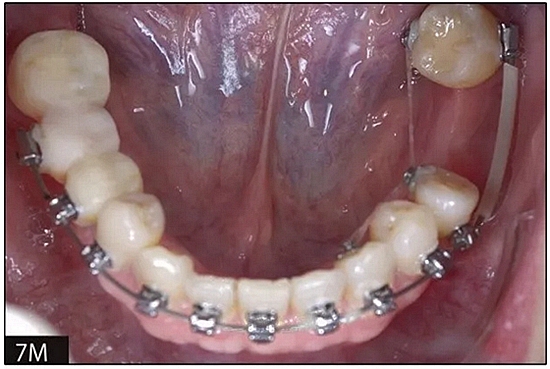

完全固定的Damon Q設(shè)備(加利福尼亞州Glendora的Ormco)與制造商指定的弓絲和附件一起使用。下頜弓,一開始放入0.014英寸的鎳鈦弓絲,5個月后放入0.014×0.025英寸的鎳鈦弓絲。舌側(cè)扣和鏈圈放置在下頜尖牙和第二前磨牙上以控制扭轉(zhuǎn)。在治療的第7個月,將下頜弓絲換成0.017× 0.025英寸的β鈦絲。另一個舌側(cè)扣和鏈圈放置在下頜左側(cè)第三磨牙上以提供近中牽引力(圖9)。在16個月的治療結(jié)束時,所有的扭轉(zhuǎn)都得到了矯正,缺牙間隙縮小到8 mm(圖8),但由于頰側(cè)骨板的嚴重吸收,牙槽嵴的寬度仍然很窄(約3 mm)(圖9)。通過正畸移動下頜左側(cè)第二前磨牙,在前磨牙之間產(chǎn)生一個種植部位。在第一和第二前磨牙之間的弓絲上放置一個推簧,并將舌側(cè)扣和鏈圈放置在第一前磨牙和第三磨牙之間(圖9),在頰側(cè)和舌側(cè)施加力。施力均為輕力,每個表面上約2盎司(28.3 cN)以控制牙根側(cè)面的吸收。

圖8